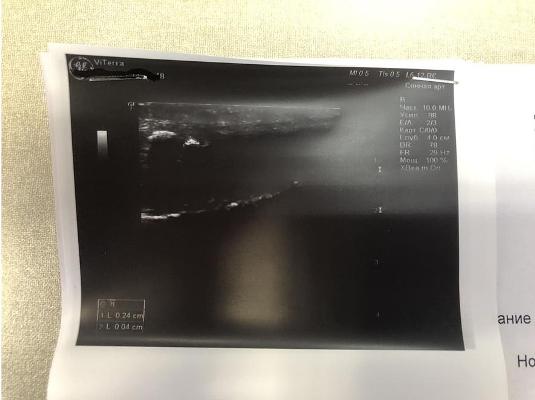

После проведённого курса лечения при контрольном УЗИ полового члена фиброзные бляшки не выявлены.